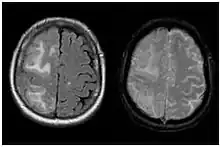

| Two MRI scans demonstrating the difference between ARIA-E (left) and ARIA-H in the parietal region (right) | |

Amyloid-related imaging abnormalities (ARIA) are abnormal differences seen in magnetic resonance imaging of the brain in patients with Alzheimer's disease. ARIA is associated with anti-amyloid drugs, particularly human monoclonal antibodies such as aducanumab.[1] There are two types of ARIA: ARIA-E and ARIA-H. The phenomenon was first seen in trials of bapineuzumab.[2]

ARIA-E refers to cerebral edema, involving the breakdown of the tight endothelial junctions of the blood-brain barrier and subsequent accumulation of fluid.[3] In a double-blind trial of the humanised monoclonal antibody solanezumab (n = 2042), sixteen patients (11 taking the drug, 5 taking a placebo), or 0.78% developed ARIA-E. A further 7 patients developed ARIA-E during an open-label extension of the trial.[4]

ARIA-H refers to cerebral microhaemorrhages (mH), small haemorrhages on the brain,[5] often accompanied by hemosiderosis.[1] mH are usually seen as small, round and low intensity lesions and are small haemosiderin deposits. Some studies define mH as being less than or equal to 10mm, while others define the cut-off as ≤ 5mm.[1] The prevalence of mH in healthy elderly people is approximately 6%, but this value increases to between 50% and 80% in elderly people with cerebrovascular disease.[6]